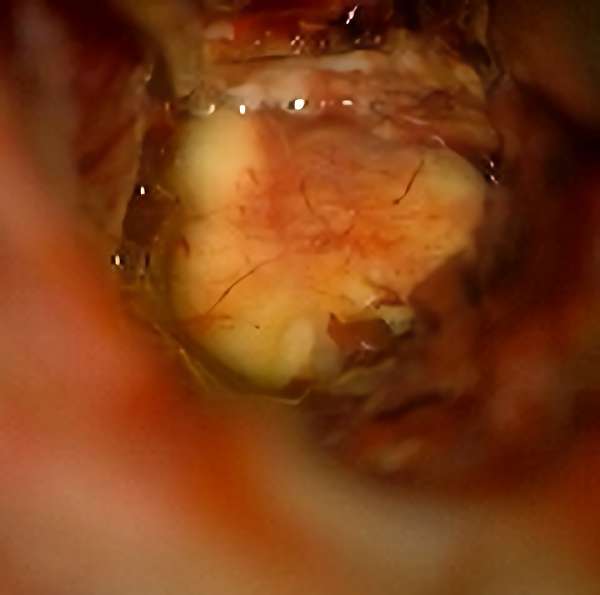

'19年11月

40代

富永

南田

基底核

海綿状血管腫

出血性

兵庫県の病院

より紹介

No.No.32 摘出前

No.No.32 摘出中1

No.No.32 摘出中2

No.No.32 摘出後

CT/MRにより完全に摘出されたことが確認された